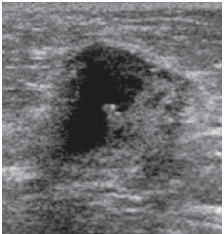

Fibroadenoma

Proliferation of fibrous (fibro) + glandular (adenoma) tissue

• Most common benign tumour

• Hormone-sensitive

• Enlarge during pregnancy/ lactation

• Decrease post menopause

Present:

• Young women (< 30)

• Mobile palpable lump

• Slow growing

• Sudden pain → hemorrhage

Oval or macrolobulated mass

Hypoechoic

Well circumscribed/ smooth margins

Homogeneous

Wider than tall

Posterior enhancement

Can have:

• *- Calcifications**

• *- Internal vascularity**